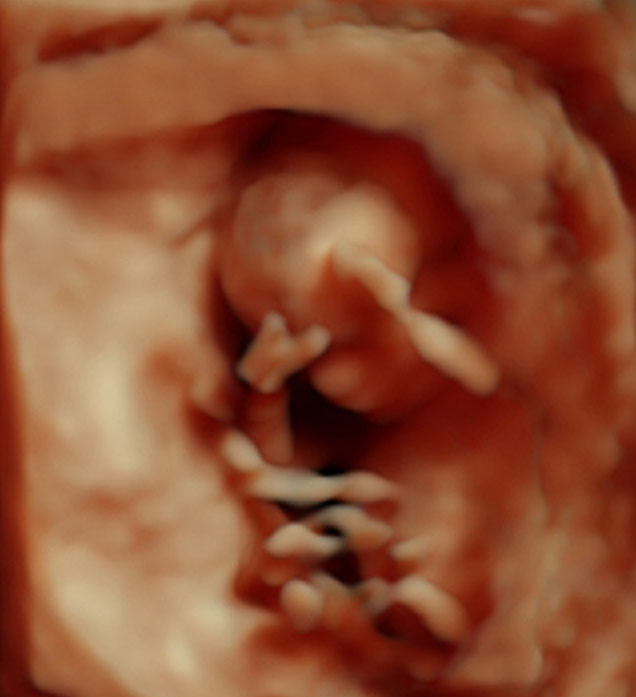

Her er nurket vårt :) 95 prosent sjans på at det blir ei jente!!!!! Lykke!!!! Alt var super bra :) Vokste som hun skulle :) Og han legen sa terminen var 25. oktober :) Men samme det! Lykke :D

Wow!! Stilig bilde! Aldri sett sånt før:):) Så fiiiiin hun er:) Gratulerer! :)

Gratulerer!! Så fint bilde, er det 3D? Visste ikke at de kunne se kjønnet så tidlig. Stas med en jente til da:-)

Takk :) Ja kjempe fornøyd med bildene...kun han her legen som har dette apparatet pluss et sykehus i nord :) Stolt av nurket <3

Dette er 3d ja :) jeg visste ikke det jeg heller, men han så det klart og tydelig :D Han er lege itillegg, så peiling på hva han ser etter :) Ja veldig stas med jente <3